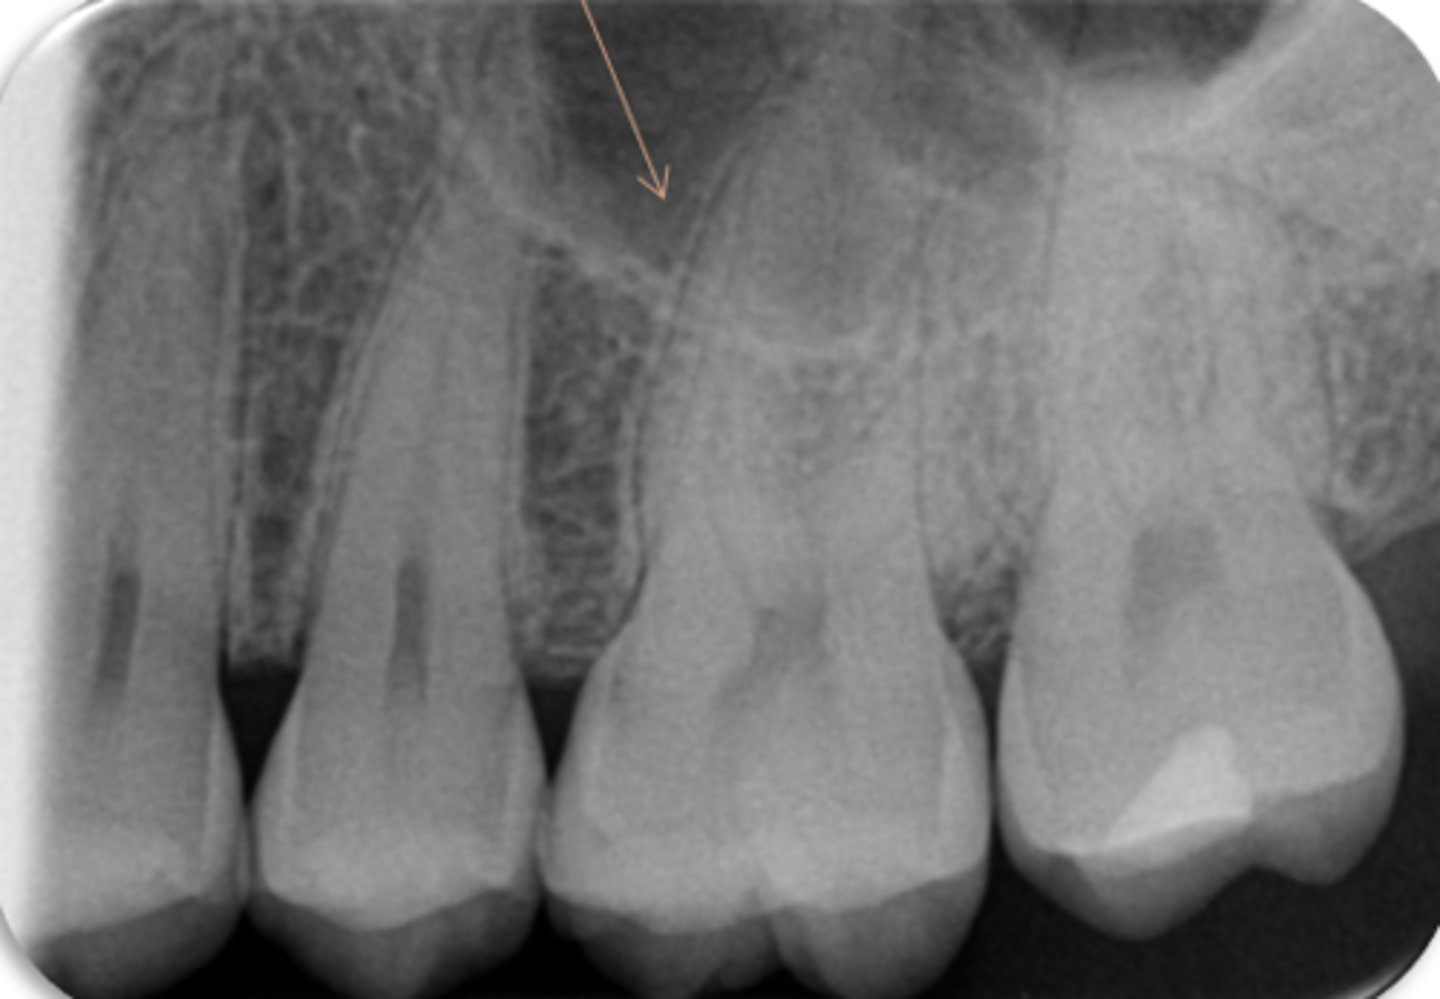

mental foramen

ID the structure: